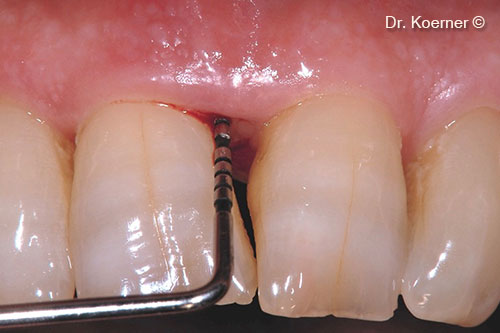

Bệnh nhân nam (61 tuổi) có tổn thương nha chu ở vùng thẩm mỹ.

Khuyết tật nha chu khu trú 11

Súng ngắn bỏ túi 9mm

Rạch da theo kỹ thuật bảo tồn nhú lợi cải tiến